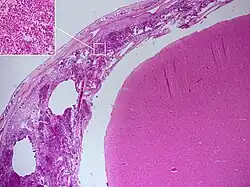

Autopsie

Le diagnostic de méningite peut être porté après la mort lorsqu'une autopsie est réalisée, montrant une inflammation de la pie mère et de l'arachnoïde avec des neutrophiles pouvant gagner le système nerveux central via les nerfs ou les vaisseaux méningés, parfois entourés de pus[36].